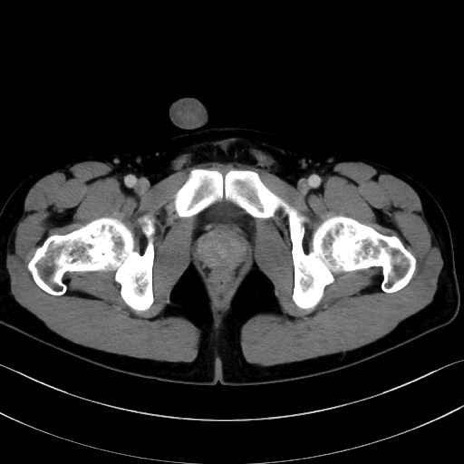

外閉鎖筋 (Obturator externus)